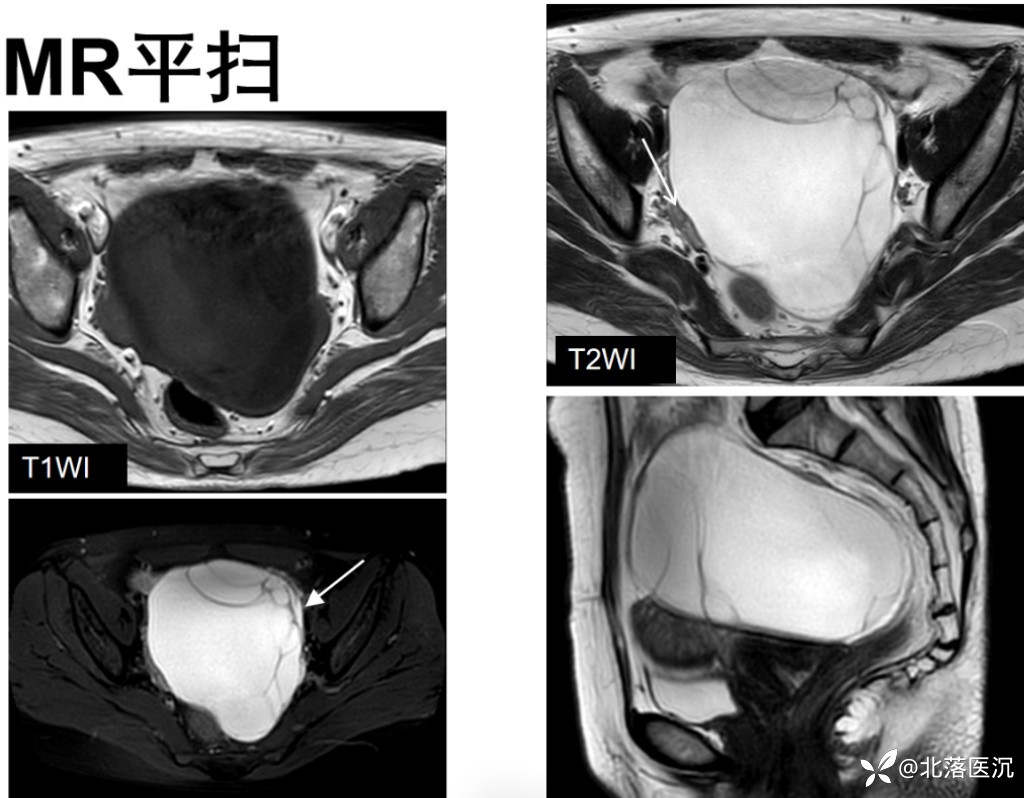

MRI表现:单囊或多囊的含脂肿块,大多包膜完整,病变内脂肪成分表现为T1WI、T2WI高信号影,脂肪抑制序列呈低信号改变;头发、牙齿及骨骼在各序列均为低信号改变;头结节信号表现多样,与头结节内含有多胚层结构有关

增强扫描:实性部分多无明显强化